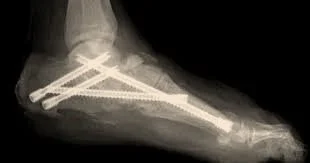

Charcot beaming involves realigning and stabilizing the collapsed foot using long intramedullary beams or screws placed across affected joints. These beams act as internal support to maintain alignment while the bones fuse and heal.

The procedure may be combined with additional fixation, soft-tissue procedures, or joint fusion depending on deformity severity.